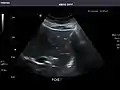

Aorta